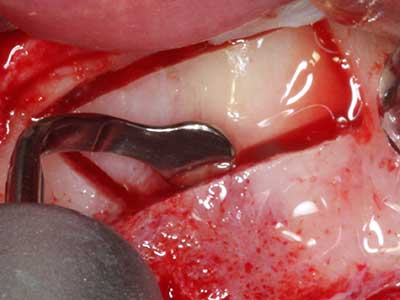

Knochengewebe ist nicht nur rein mineralisch, sondern auch in wesentlichen Anteilen aus Kollagenfasern aufgebaut. Dies gewährleistet neben einer guten Druckfestigkeit eine gewisse Flexibilität, welche für die Durchführung von Augmentationen genutzt werden kann. Bei der klassischen Expansionsplastik im Sinne eines Bone Splittings wird der atrophierte Kieferkamm in seiner Längsachse gespalten und nach Erreichen einer ausreichenden Osteotomietiefe vorsichtig aufgedehnt (Abb. 13-16), idealerweise ohne den Kiefer wesentlich zu deperiostieren (Brugnami, Caiazzo et al. 2014, Stricker, Fleiner et al. 2014). Bewährt haben sich Schrauben- und Plattensysteme mit zunehmender Expansionsdistanz, um die beiden Knochenlamellen unterhalb der Bruchschwelle voneinander zu distanzieren. In der Regel werden Restknochenbreiten von mindestens 3-4 mm gefordert (Chiapasco, Zaniboni et al. 2006), um eine ausreichende Flexibilität und knöcherne Bedeckung der einzubringenden Implantate zu gewährleisten. Ggf. kann eine ein- oder beidseitige vertikale Entlastungsosteotomie die Flexibilität verbessern. Als Alternative zur klassischen Technik wurde eine Kombination mit weiteren augmentativen Techniken vor allem auf der bukkalen Seite beschrieben.

Mittels Piezosägen erfolgt die Anlage des Splittings besonders schonend und ohne wesentliche Dimensionsverluste, so dass sich keine signifikanten Unterschiede von Implantaten im gesplitteten Kiefer im Vergleich zum nicht defizitären Alveolarkamm gezeigt haben (Chiapasco, Zaniboni et al. 2006, Danza, Guidi et al. 2009). Gerade beim lokal begrenzten und tiefen Splitting ist jedoch stets auf eine ausreichende Wasserkühlung zu achten, um thermische Belastungen in den apikalen Osteotomiebereichen zu vermeiden.